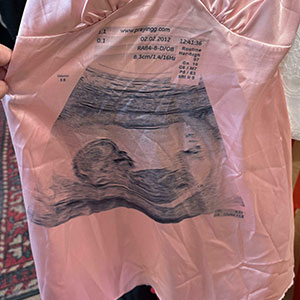

Grandpa’s Shirt Came With A Surprise — He Was Already Wearing It!